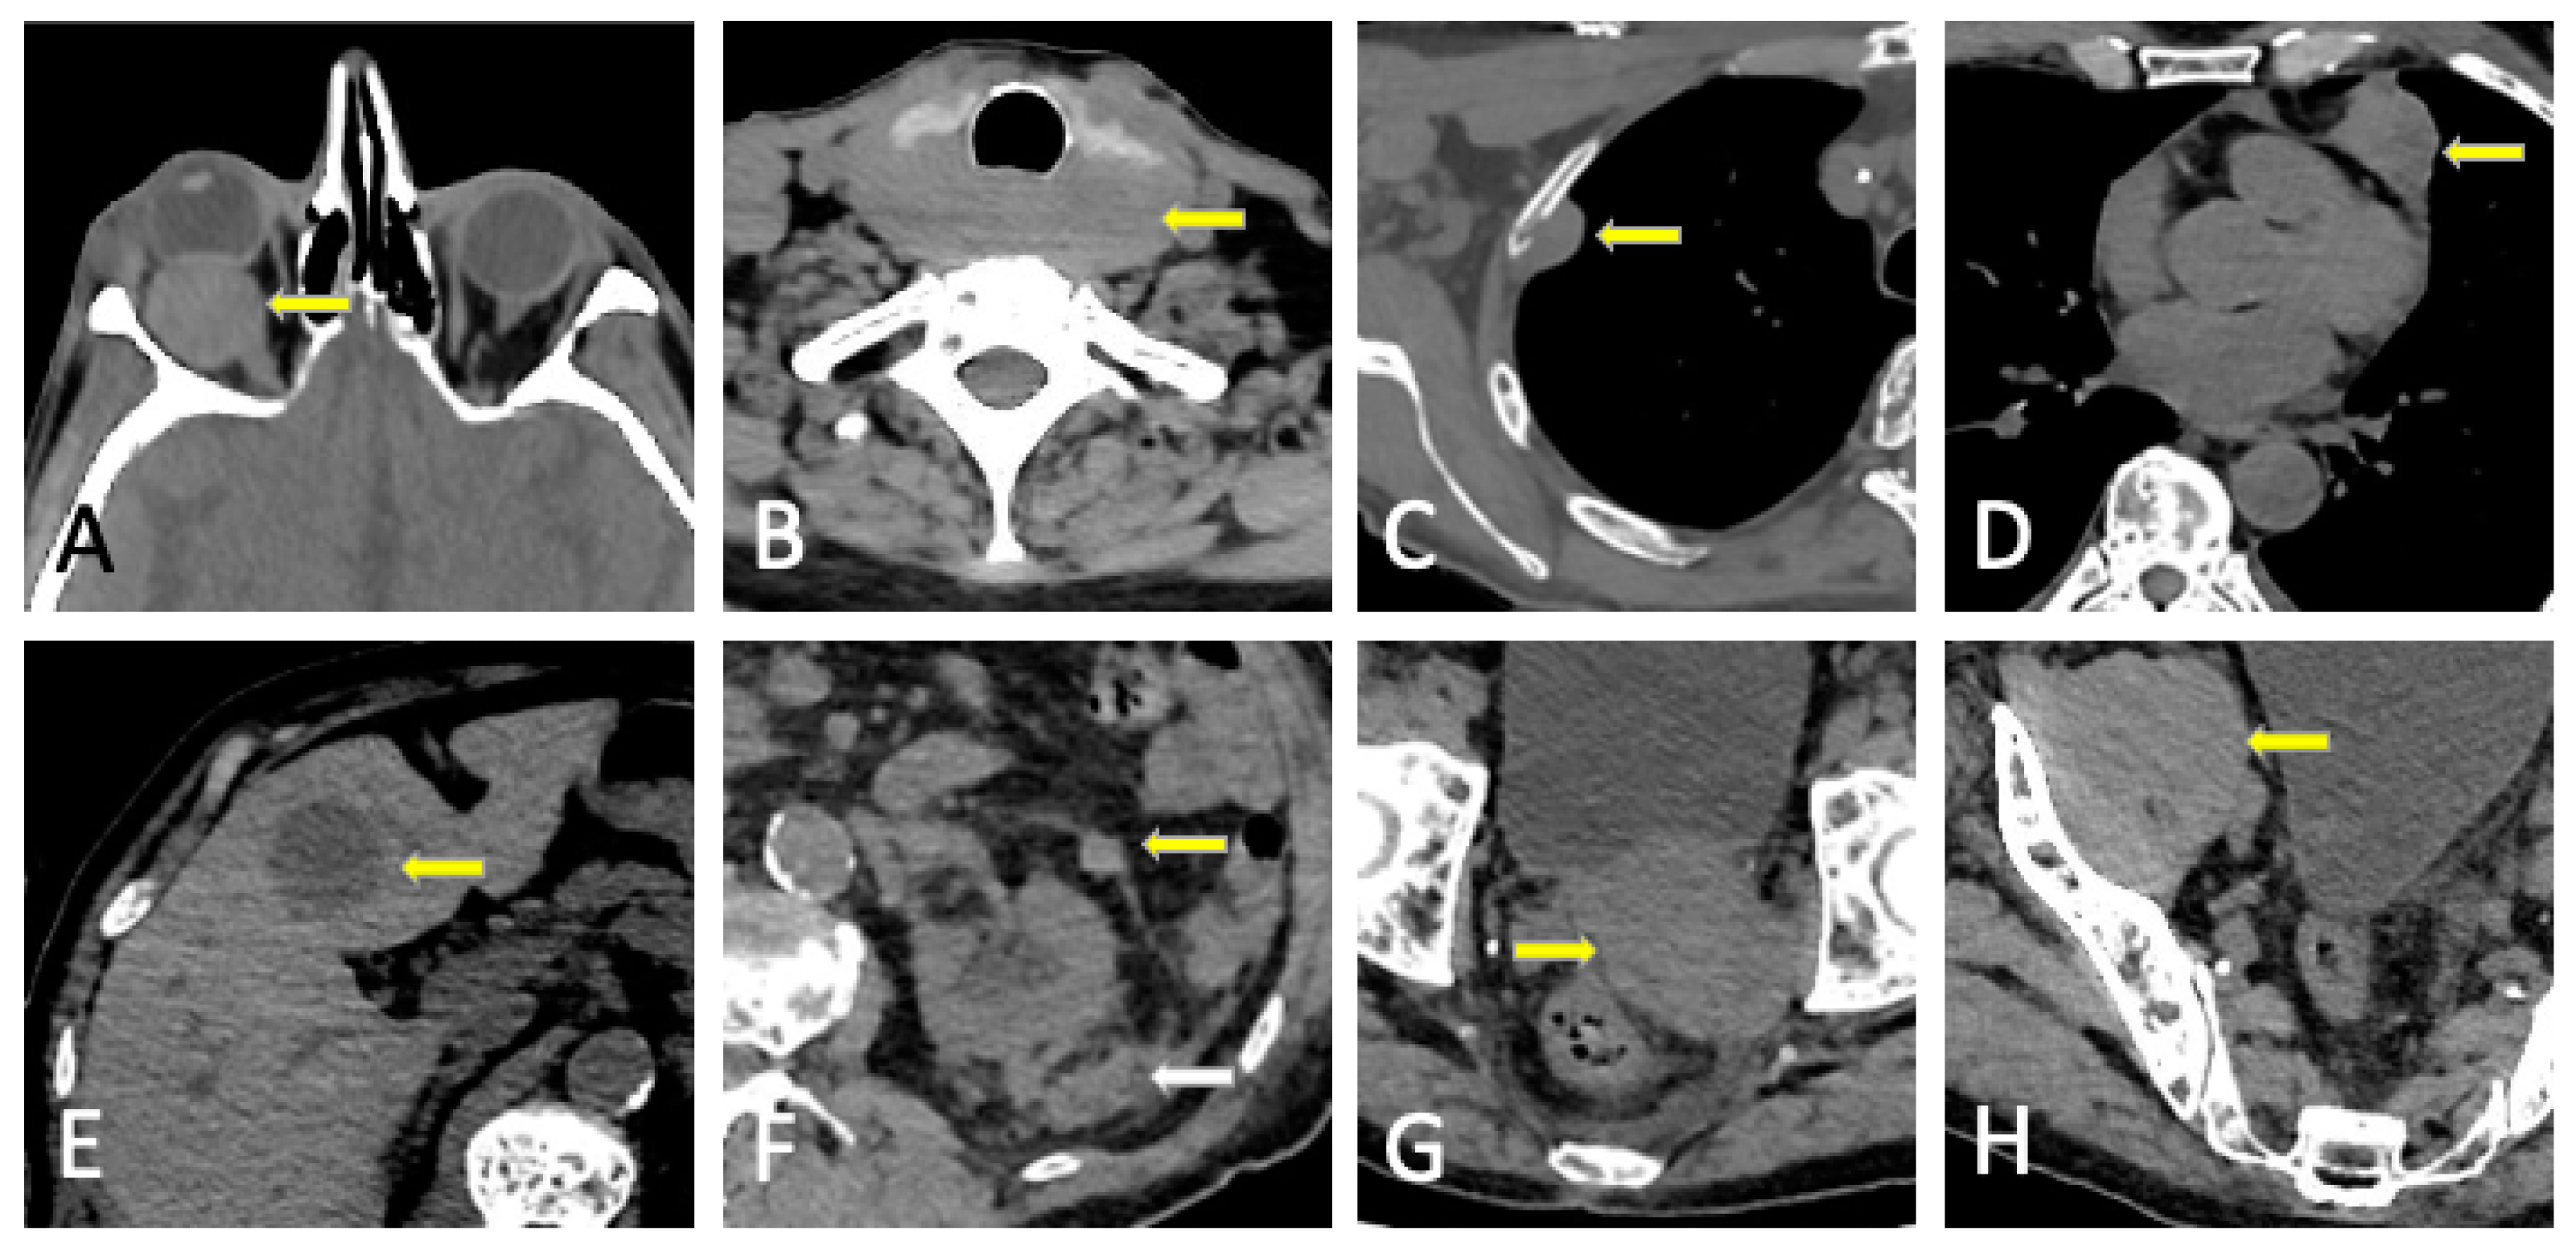

- Hall, M.N.; Jagannathan, J.P.; Ramaiya, N.H.; Shinagare, A.B.; Van Den Abbeele, A.D. Imaging of Extraosseous Myeloma: CT, PET/CT, and MRI Features. Am. J. Roentgenol. 2010, 195, 1057–1065. [Google Scholar] [CrossRef]

- Cho, R.; Myers, D.T.; Onwubiko, I.N.; Williams, T.R. Extraosseous Multiple Myeloma: Imaging Spectrum in the Abdomen and Pelvis. Abdom. Radiol. 2021, 46, 1194–1209. [Google Scholar] [CrossRef]